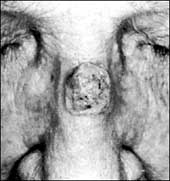

السرطانات الجلدية شائعة خاصة لدى ذوي البشرة البيضاء الذين يعيشون في المناطق الشمسية

الدكتور عبد الله العيسى: للوقاية من سرطانات الجلد عليك تجنب أشعة الشمس

تعتبر سرطانات الجلد بشروية الخلايا من السرطانات الجلدية الشائعة خاصة لدى الناس ذوي البشرة البيضاء الذين يعيشون في مناطق مشمسة، وتكمن أهمية هذه السرطان.........